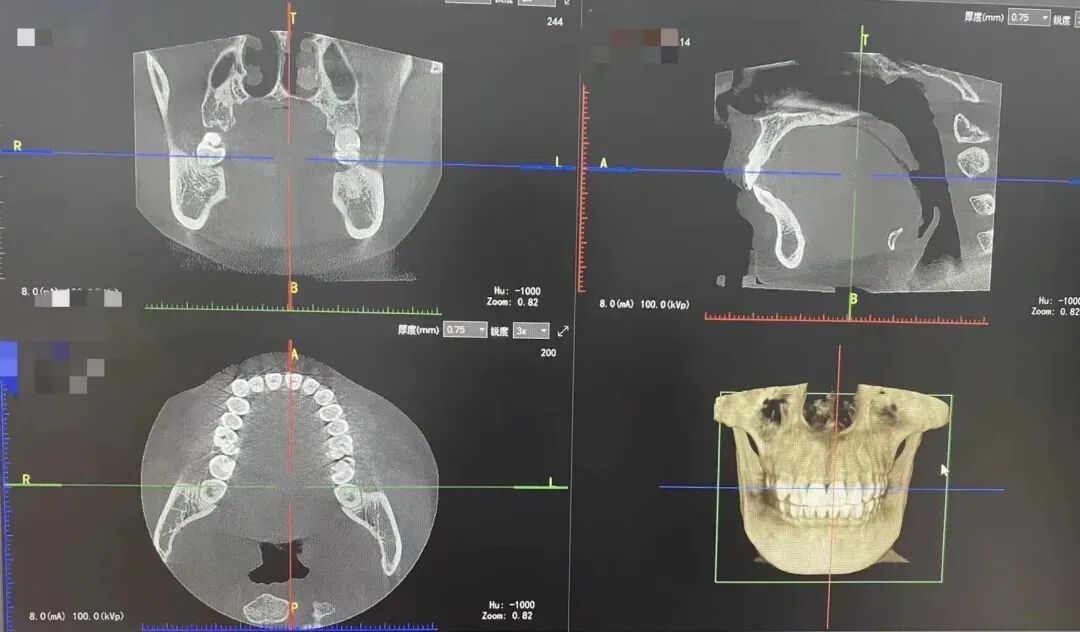

4.口腔CBCT的临床应用?

(7)种植牙。CBCT设备可以辅助种植手术的设计,制作种植导板,精确控制种植体的位置、方向、长度、直径等,最大程度利用患者现存骨量,优化种植体的位置,避免在种植手术过程中不慎破坏神经、鼻窦等解剖结构而导致颜面神经麻痹、鼻窦炎等并发症。使种植手术更安全便捷,确保手术及后期修复的成功。

(8)颌面外科。

(9)正畸等。